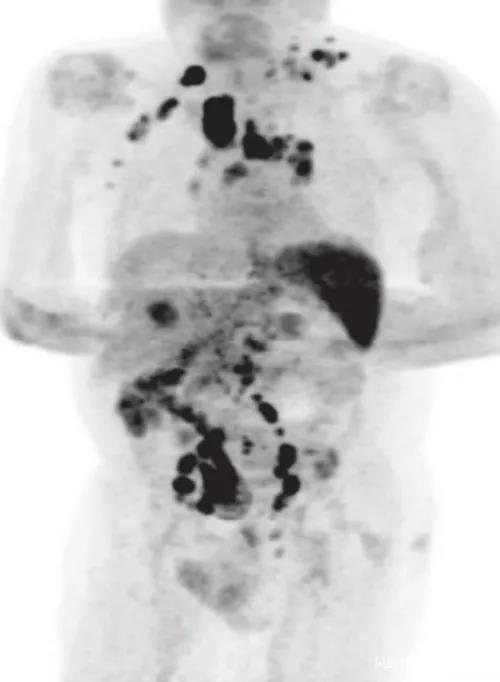

此后,男子停止了一切免疫治疗,带着病痛生活。2020年年中,男子的身体突然之间暴瘦,并且全身淋巴结肿大,他赶紧到医院检查,结果确诊罹患经典型霍奇淋巴瘤,PET-CT扫描提示疾病分期为3期。霍奇淋巴瘤是一种恶性肿瘤。也就是说,男子此时是一名癌症晚期患者。CT照片也显示,癌细胞扩散到了他身体的各个地方。

到此,男子的身上出现了三种疾病:末期肾衰竭,晚期癌变的霍奇金淋巴瘤,以及新冠肺炎。这任何一种疾病放在一位61岁老人的身上都是十分凶险的,不难想象他那时所承受的煎熬和病痛。住院11天后,男子的症状有所缓解,决定回家休养。或许在他看来,放弃治疗未尝不可。事实也是如此,男子在回到家后再也没有接受过任何皮质类固醇和免疫化疗。四个月后,男子回医院复查。PET-CT扫描却提示,他体内的大部分肿瘤竟然神奇地都消失了。更为夸张的是,与肿瘤有关的生物指标直接下降了约9成。反复检查后,医生们最终确认,男子的癌症痊愈了。而他的新冠检测也显示为阴性,男子体内的新冠病毒也消失了。